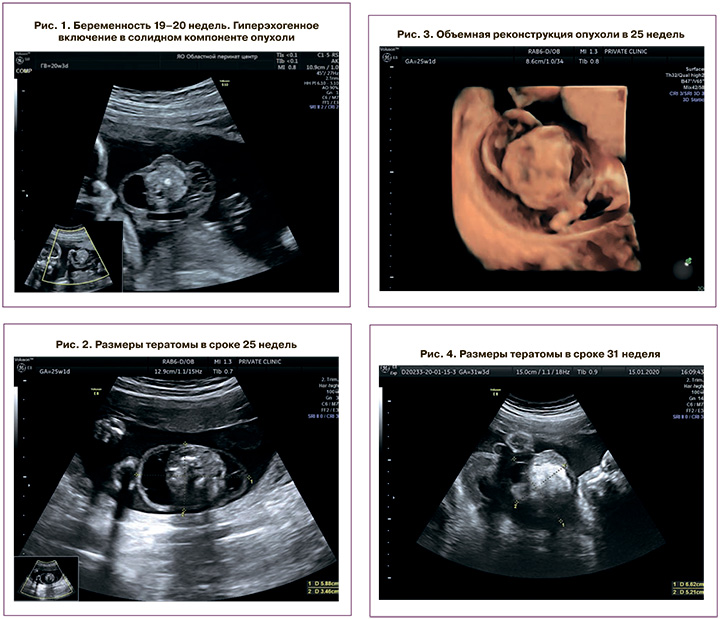

Беременная Л., 35 лет. Образование пуповины впервые было выявлено при проведении второго ультразвукового скрининга в 20 недель. Беременная была направлена на перинатальный консилиум. Проведенный первый комбинированный скрининг патологии не выявил. Женщина здорова, в браке, беременность третья, родов не было.

Фетометрические показатели плода соответствовали 20 недель и 1 день. Масса плода – 332 г. Изучение анатомии плода патологии не выявило. На уровне 40 мм от пупочного кольца на пуповине обнаружено образование 47×42 мм преимущественно солидного строения с кистозными включениями по его периферии. В солидном компоненте визуализировались гиперэхогенные включения, дающие акустические тени (рис. 1). В режиме ЦДК образование аваскулярное. Пуповина имела 3 сосуда. Сосуды пуповины располагались по периферии солидного компонента образования. Пульсационный индекс (ПИ) в обеих артериях составил 1,33 и 1,31. В непосредственной близости от образования, ближе к брюшной стенке плода, на пуповине дополнительно обнаружено тонкостенное анэхогенное образование 17×14 мм, расцененное как киста. Заключение перинатального консилиума: «Беременность 20 недель. Образование пуповины (тератома?)».

Последующие ультразвуковые исследования были проведены в 25 недель и 31 неделю. В динамике отмечен рост опухоли.

В сроке 25 недель размер образования составил 59×34 мм (рис. 2, 3). Изолированная от образования киста также увеличилась до 24×14 мм. Показатели кровотока в артерии пуповины: ПИ (в обеих артериях) – 1,02 и 1,19;

В сроке 31 неделя – размер образования составил 66×52 мм (рис. 4). Изолированная от образования киста – 33×28 мм. Показатели кровотока в артерии пуповины: ПИ (в обеих артериях) – 0,76 и 0,85 (рис. 5).

Последующий ультразвуковой контроль был запланирован через 4 недели, однако незадолго до него, в 35 недель, произошла антенатальная смерть плода. Родилась мертвая недоношенная девочка массой 2800 г, длиной 48 см. Размер образования на пуповине – 10×8 см. Клинико-патолого-анатомический эпикриз: «Причиной смерти недоношенного новорожденного от 3 беременности, 1 родов, вероятно, послужила антенатальная гипоксия, обусловленная сдавлением сосудов пуповины тератомой». Микроскопия образования пуповины подтвердила наличие организмоидной зрелой тератомы (рис. 6).